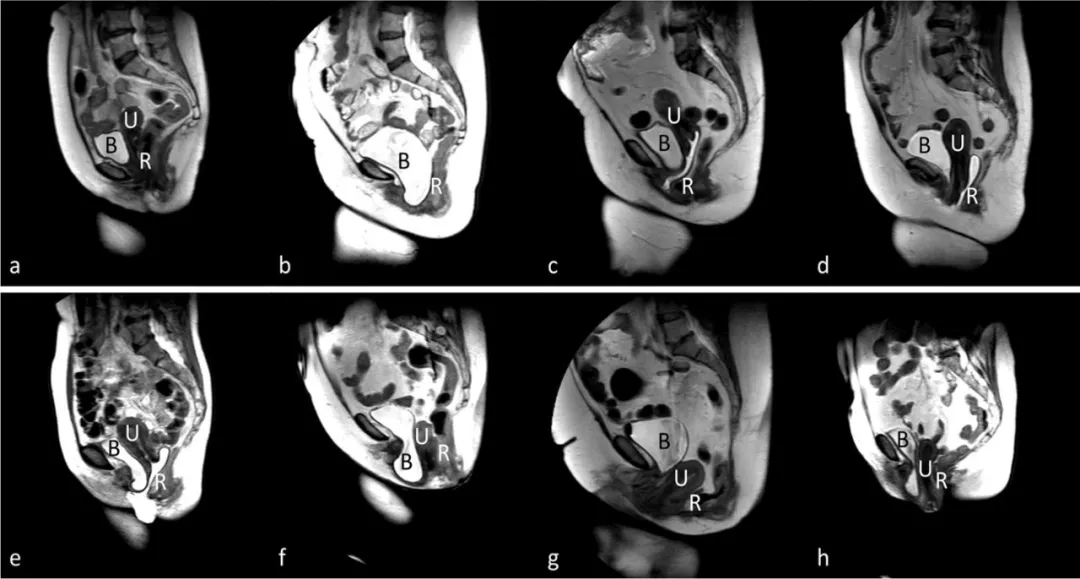

磁共振在女性盆腔脏器脱垂中的应用

图片尺寸1080x579